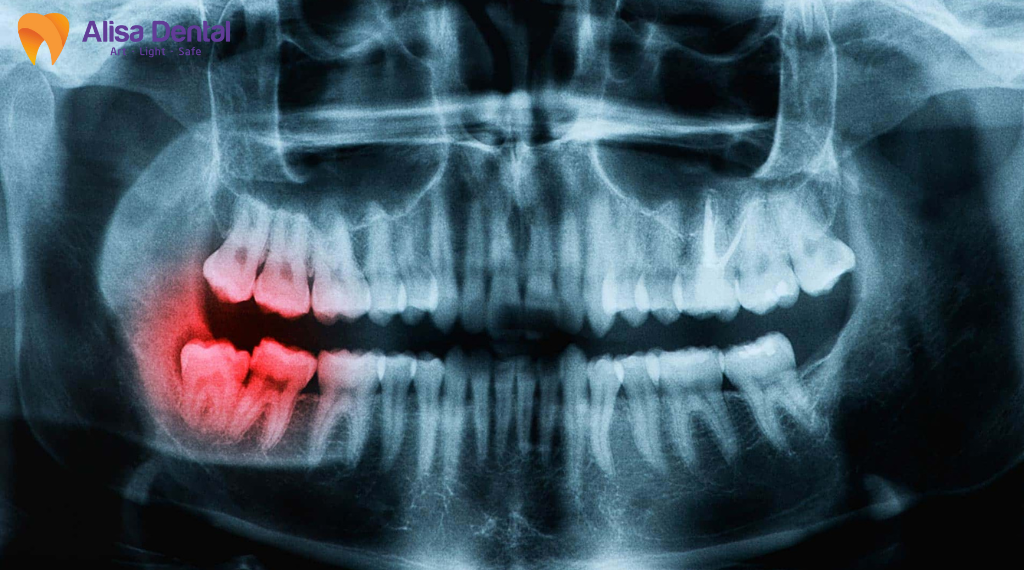

Đặc điểm mọc lệch, mọc ngầm của răng khôn

Răng khôn thường nằm sâu trong xương hàm, mọc lệch hoặc chèn ép răng kế cận, khiến quá trình nhổ phức tạp hơn so với răng thông thường. Việc phải bóc tách mô rộng, can thiệp vào xương hoặc chia nhỏ thân răng làm vùng tổn thương lớn hơn, kéo dài thời gian lành thương. Đây là yếu tố nền khiến nguy cơ viêm, sưng kéo dài hoặc khó hồi phục cao hơn, ngay cả khi quy trình được thực hiện đúng.